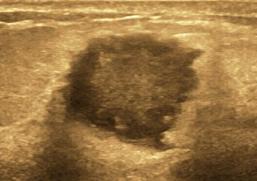

3.乳腺结节的边缘。

分为:光整和不光整(模糊、成角、微小分叶、毛刺等)。边缘光整是指:结节的边缘与周围组织界限清晰,往往是良性结节的特征。结节边缘不光整往往是乳腺癌的征象,指的是:模糊(结节的部分边缘无清晰的边界)、微小分叶(结节边缘出现锯齿状结构)、成角(结节边缘部分或全部形成锋利的角度,通常为锐角)、毛刺(从结节的边缘放射状的锐利细线)。

结节的边缘成角,是恶性的表现